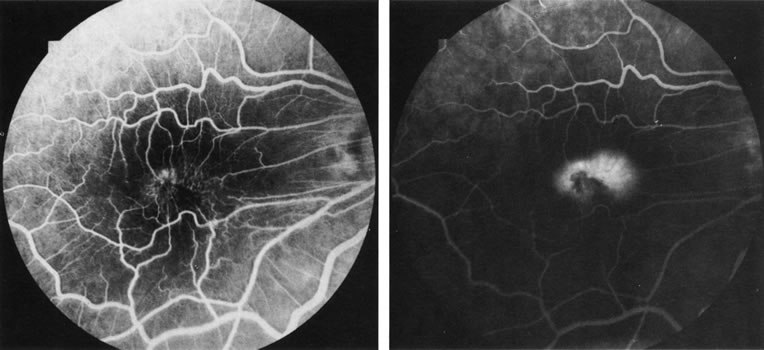

In patients with a shallow neurosensory detachment, the Amsler grid test and visual acuity may be normal. If there is subtle elevation of the neurosensory retina on biomicroscopy examination, FA may demonstrate a CNV before it is symptomatic. It is often easier to evaluate both RPE and neurosensory detachments with good stereoscopic FA pictures than with direct examination.5 Consequently, FA can be helpful in determining the presence and extent of these processes. This is particularly important in patients with CNV due to AMD, because its aggressive course often requires prompt intervention to save central vision.6,7 Furthermore, FA helps in recognizing two types of CNV: classic and occult. Classic CNV consists of a well-defined neovascular membrane, which is apparent in the early phase of the angiogram and shows late leakage of dye beyond its boundaries (Fig. 7 and 8). Occult CNV is seen on by FA as an area of late hyperfluorescence of undefined origin or as a neovascularized PED (Fig. 9 and 10 ). Mixed-type CNV is predominately classic or minimally classic depending on whether the classic component is more or less than 50% of the entire lesion (Fig. 11).

The FA can also distinguish CNV from simulating lesions. For example, a dark mound of blood due to hemorrhage from a CNV will block choroidal fluorescence, whereas vascular tumefactions such as choroidal hemangiomas leak fluorescein. Choroidal melanomas frequently block early choroidal fluorescence and then leak fluorescein from their intrinsic vascular network in later phases of FA. TREATMENT FA is vital for the management of CNV.51–55 It can define the borders of the membrane and help localize the fovea. The final determination whether the CNV is subfoveal, juxtafoveal, or extrafoveal requires use of both FA to outline the membrane with respect to the retinal vasculature and clinical examination to define the precise location of the fovea (Fig. 16). Some patients, particularly those with high myopia, have an indistinct foveal avascular zone on FA. Other FA clues, such as the location of the macula lutea pigment, can be deceptive, because fixation does not necessarily correspond to the center of the macula lutea. The value of FA is also limited in cases of occult or poorly defined CNV, in which the exact location of the leaking CNV vessels cannot be angiographically determined (Fig. 17), and in patients with subretinal hemorrhage that obscures the membrane. In these patients, ICG angiography may be the most precise means of localization.

Conventional laser thermophotocoagulation is the treatment of choice for extrafoveal, well-defined, classic CNV. Photodynamic treatment (PDT) is the treatment of choice for subfoveal, predominantly classic CNV. FA is used to localize the lesion in relation to the fovea, classify the subtype, choose the type of procedure, and guide the treatment (Figs. 18, 19, and 20).56–73